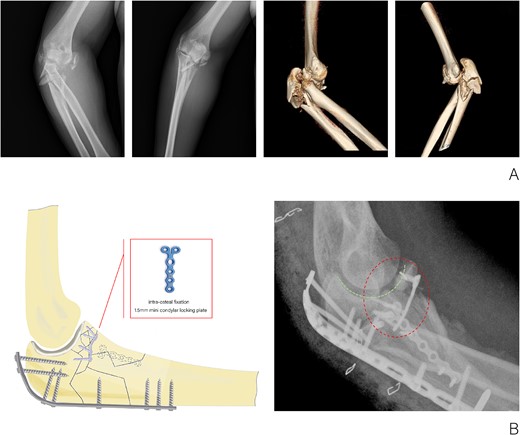

The patient, a 36-year-old male, sustained a direct trauma to the elbow joint resulting from a forceful fall and impact with the ground. The diagnosis revealed a right Monteggia fracture, accompanied by posterior elbow dislocation and ulnar nerve injury. Examination revealed no external wounds on the elbow joint. Furthermore, preoperative assessment confirmed that the blood supply, ulnar nerve, radial nerve, and central nerves of the affected limb remained intact. A plaster was used to fix the elbow in the flexor position temporarily. Three-dimensional CT reconstruction clearly indicated an O’Discoll III fracture of the coronoid process, which was fragmented into three discrete bone fragments. Additionally, there was evidence of a comminuted fracture of the olecranon as well as a fracture of the radial head (Fig. 1A).

(A) X-ray and CT three-dimensional reconstruction examination of elbow fracture. (B) Diagram of intra-osteal fixation of comminuted coronoid process fracture with mini plate and postoperative X-ray examination of the elbow.

The surgical procedure was conducted under a combination of brachial plexus block anesthesia and general anesthesia, with the application of an upper arm tourniquet. A posterior cubital incision was made to access the fracture and safeguard the ulnar nerve. The primary fracture fragments of the coronoid process measured 8 × 9, 15 × 9, and 10 × 9 mm2, respectively. A three-hole, 1.5-mm mini condylar locking plate and a 1.0-mm Kirschner wire were utilized to stabilize the coronoid process in conjunction with the olecranon intra-osteally, aiming to reconstruct the joint surface. A proximal dorsal ulna locking compression plate was employed to secure the olecranon to the distal ulna from the dorsal aspect. Additionally, a large medial fracture block of the proximal ulna was stabilized using a six-hole, 1.5-mm mini condylar locking plate. Subsequently, the radial head was exposed and its fracture was stabilized with a 2.0-mm cannulated screw. The elbow drawer test and stress test results were negative, suggesting the absence of instability related to injuries of the medial and lateral collateral ligaments and the anterior capsule. Consequently, exploration of the collateral ligaments was deemed unnecessary and external fixation of the elbow was not performed. The duration of the surgical procedure was approximately 100 min.